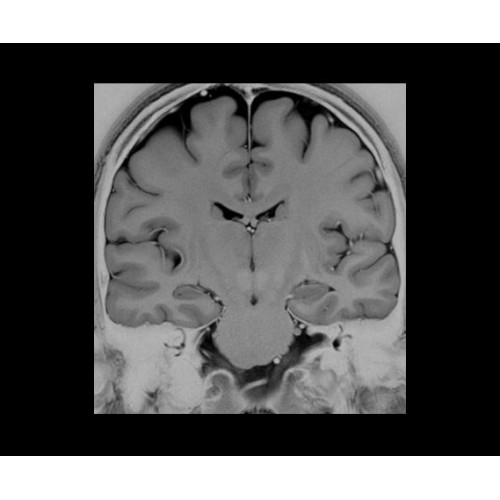

SIGNA PET/MR 3.0T — это гибридная система, в которой совмещаются две принципиально разные технологии — магнитно-резонансную томографию (МРТ) и позитронно-эмиссионную томографию (ПЭТ). Система отличающийся высокой чувствительностью и эффективностью и предназначена для диагностики в области онкологии, неврологии, кардио-васкулярных исследований, исследований воспалительных процессов.

Компания GE Healthcare представляет революционную, полностью интегрированную систему SIGNA PET/MR1, в которой сочетаются времяпролетная технология (TOF) и возможности напряженности магнитного поля 3.0 Тл. Мы поможем вам поднять исследования на более высокий уровень. SIGNA PET/MR позволяет достичь впечатляющей точности и скорости исследований, а благодаря новейшей технологии реконструкции Q.Clear2 качество изображений улучшается в два раза. Кроме того, в систему включен полный набор клинических приложений и гибких катушек для проведения любых видов исследования, открывая для вас возможности визуализации, о которых вы даже не догадывались.

Кроме того, в результате использования технологии TOF и инновационной технологии реконструкции Q.Clear вы сможете добиться прекрасного соотношения сигнал/шум. А благодаря технологии нулевого времени эхо (ZTE) визуализировать костную структуру без ионизирующего излучения. Все эти разработки для улучшения качества сканирования и точности анализа помогут вам использовать весь потенциал ПЭТ/МРТ.

• Специальный пакет приложений для измерения и сравнения объемных изображений ЦНС с нормами поможет вам в диагностике нейродегенеративных заболеваний, а дополнительные инструменты визуализации — в постановке точного диагноза с помощью бета-амилоидов и радиоизотопных маркеров ФДГ.